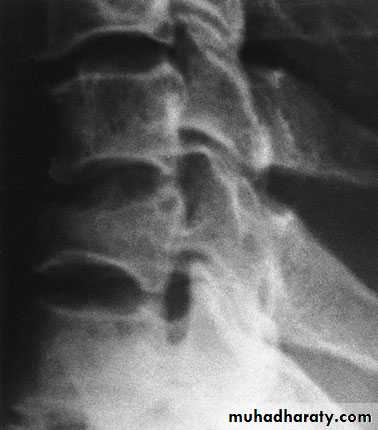

Thoracic Spine X Ray

Lateral radiograph

A/P radiographIn general a typical vertebra consists of :